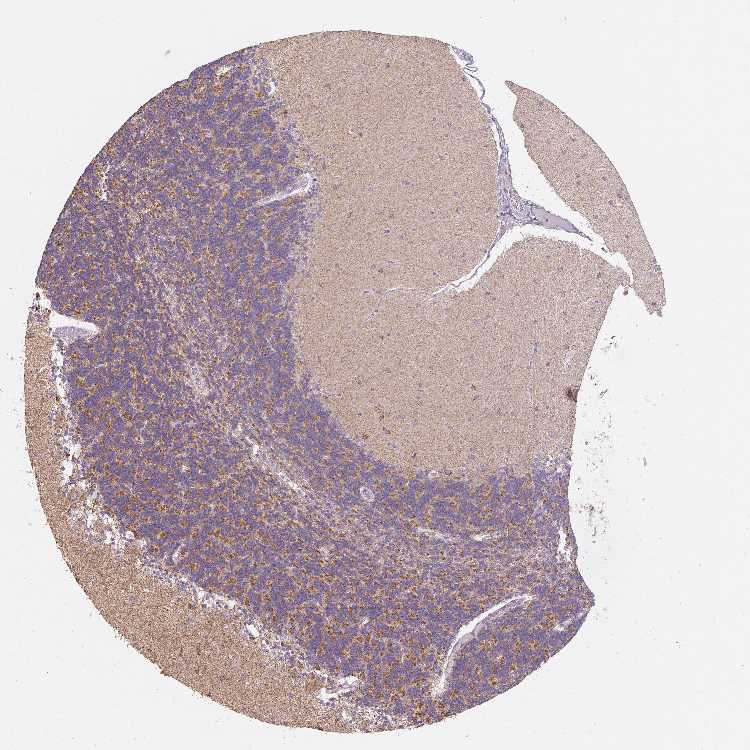

CEREBELLUM - Antibody stainingi

Antibody staining in the annotated cell types in the current human tissue is reported as not detected, low, medium, or high, based on conventional immunohistochemistry profiling in selected tissues. This score is based on the combination of the staining intensity and fraction of stained cells.

Each image is clickable and will lead to virtual microscopy that enables deeper exploration of all samples and also displays staining intensity scores, fraction scores and subcellular localization as well as patient and tissue information for each sample.

Antibody HPA054582

Purkinje cells Medium

Cells in granular layer Medium

Cells in molecular layer Medium